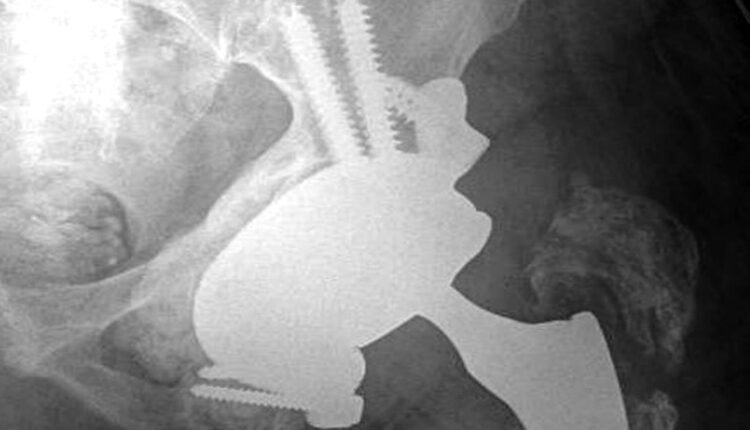

Il nuovo servizio consentirà al cittadino la consultazione e lo scarico di referti e immagini radiologiche dal portale servizi ‘Abruzzo sanità online’.